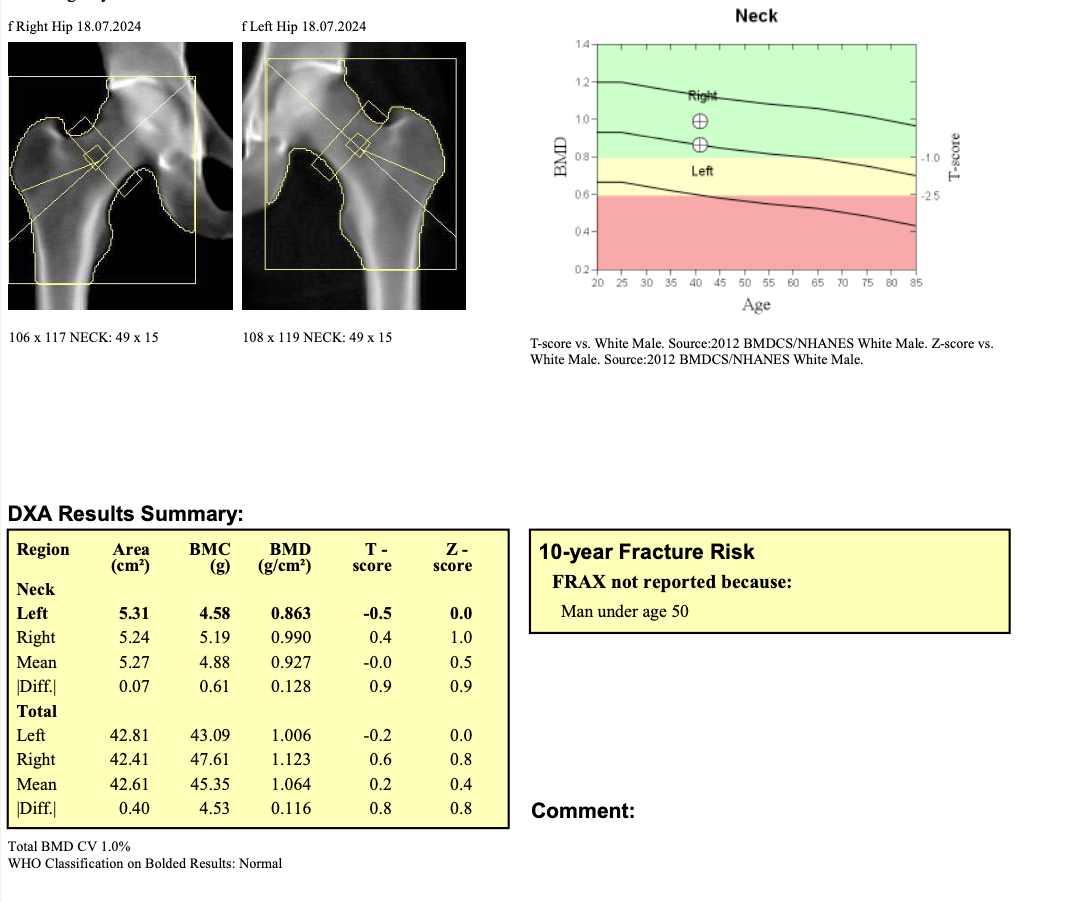

Example Report: